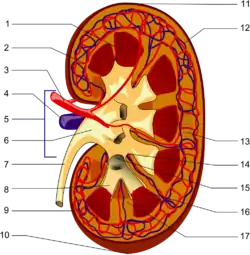

Urinary System

Toxic nitrogenous wastes accumulate as proteins and nucleic acids are broken down and used for other purposes. The urinary system rids the body of these wastes. The urinary system is also directly involved in maintaining proper blood volume (and indirectly blood pressure) and ion concentration within the blood. One other contribution is that the kidneys produce a hormone (erythropoietin) that stimulates red blood cell production. The kidneys also play an important role in maintaining the correct water content of the body and the correct salt composition of extracellular fluid. External changes that lead to excess fluid loss trigger feedback mechanisms that act to inhibit fluid loss.

Excretory System is responsible for removing wastes, excess water and salt in the urine. Regulates the volume and pH of the internal environment. The human excretory system maintains homeostasis by removing metabolic waste such as water, salt and metabolite concentrations in the blood. The kidneys, which are the primary excretory organs, are major organs of homeostasis because they excrete nitrogenous wastes, and regulate water-salt balance and acid base balance. This section will examine the kidney in details.